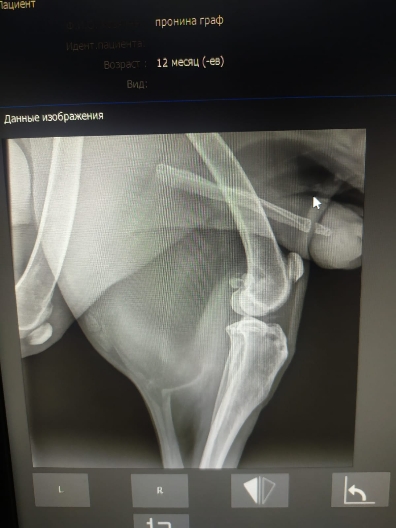

Рентген и анализы.

Рентген легких бы еще в другой позиции и на эхо к кардиологу сходить.

Просто на рентгене вопрос к форме сердца.... тогда может рентген на спине попозже